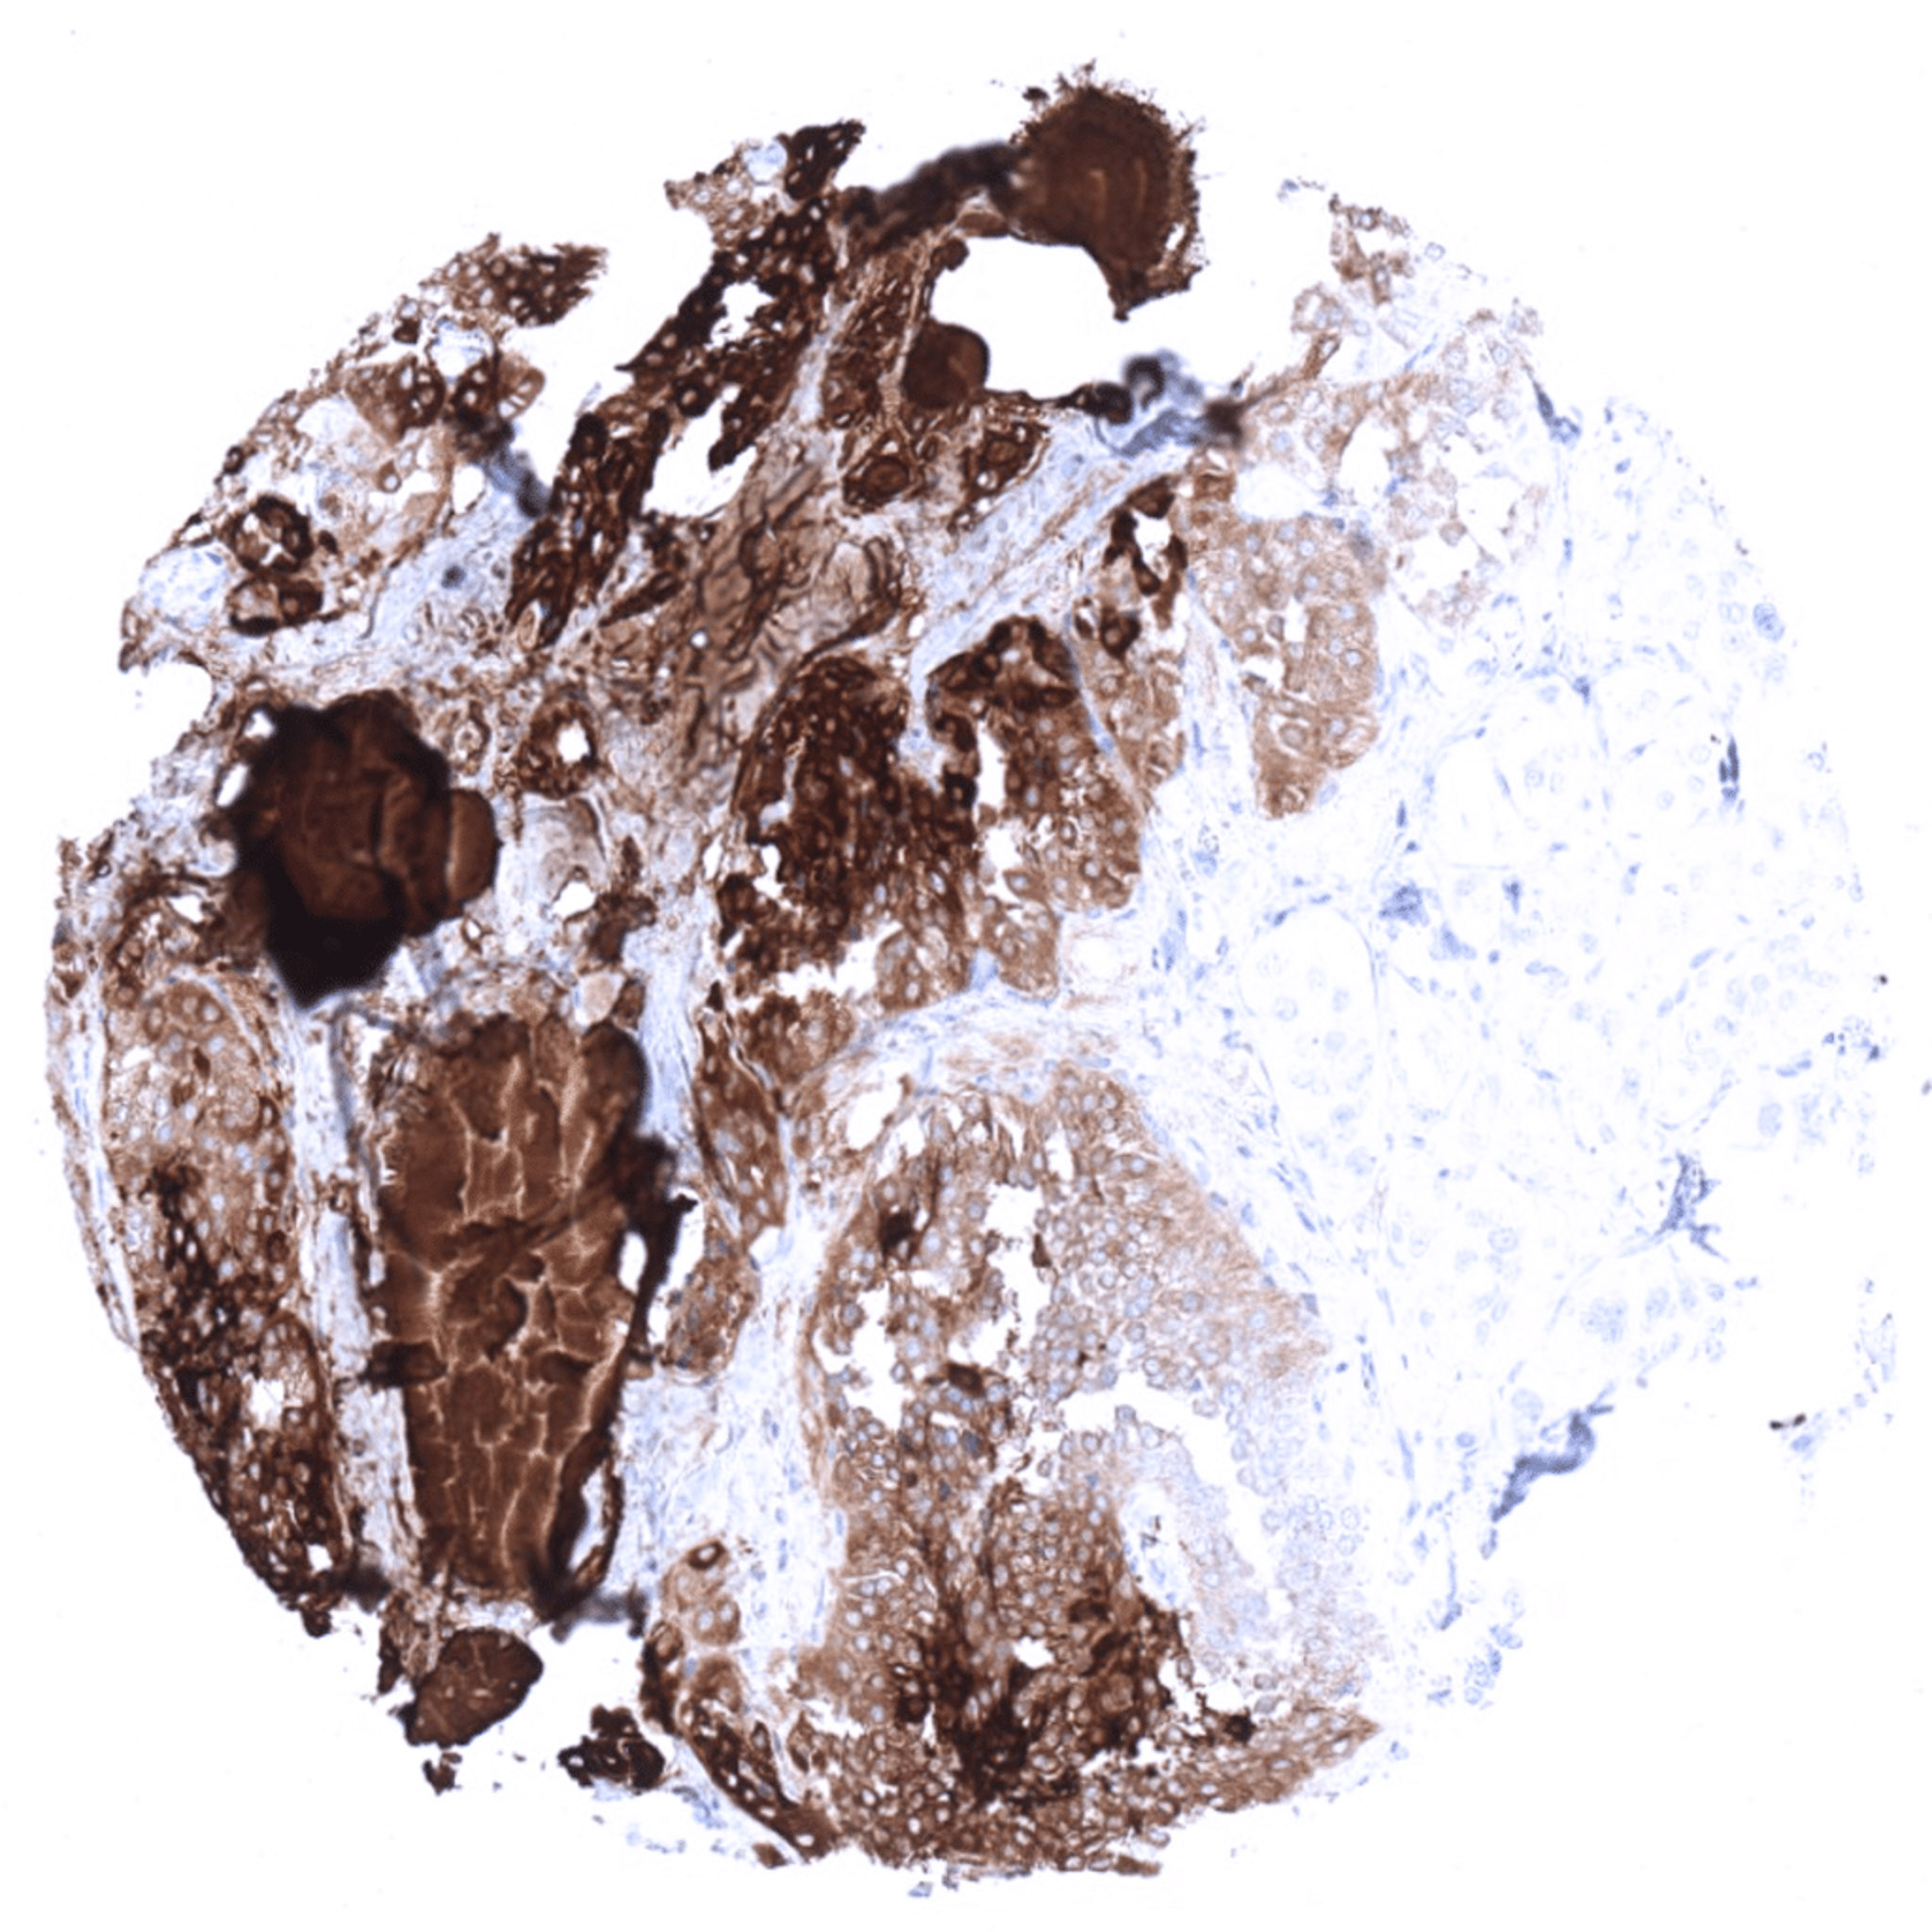

Papillary thyroid cancer with intense thyroglobulin positivity and extensive stroma contamination.